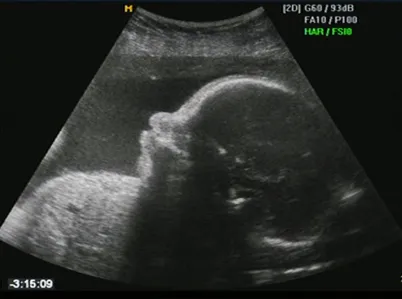

Clomid is one of the most popular infertility treatment drugs available on the market, prescribed to hundreds of women daily. However, mounting evidence shows that this drug may increase the risk of birth defects in unborn children.

Clomid is a popular fertility medication, which stimulates egg production and ovulation in women. However, Clomid has been accused of causing numerous severe birth defects in unborn fetuses including: